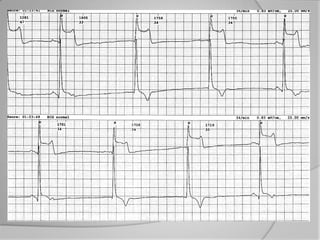

 ECG : EN DEHORS DE LA DOULEUR

 ECG : PENDANT LA DOULEUR MODIF

l’électrocardiogramme initial :

- syndrome coronaire aigu avec sus-

décalage persistant de ST (SCA ST+) qui

signifie occlusion coronaire totale)

- syndrome coronaire aigu sans sus-

décalage de ST (SCA NST-) qui regroupe

l’angor instable et les infarctus sans Q.